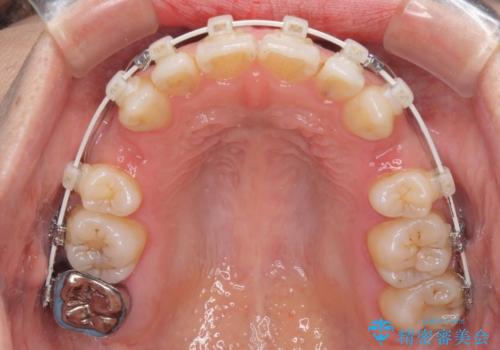

- 矯正装置

- 審美装置

- 唇の閉じにくさを気にして来院された患者様です。

上下左右第一小臼歯4本を抜歯し、ワイヤー装置にて口元を引っ込めるよう矯正治療を行うこととしました。